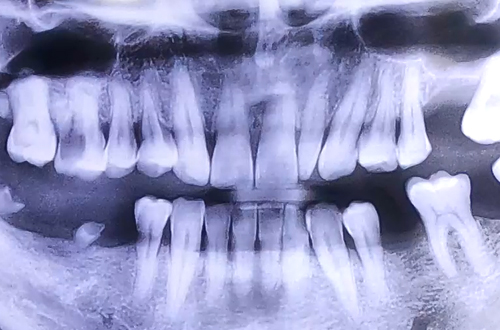

AFTER

양쪽 모두 어금니 상태가 좋지 못하여 음식을 제대로 드시지 못하는 상태의 환자분 진료 내용입니다.

치아가 온전치 못하여 음식을 씹는 데에 불편함이 따르면 그만큼 삶의 질도 크게 떨어지게 되는 것이 사실인데요.

저희 더365치과는 임플란트에 특화된 진료를 진행하고 있어, 임플란트 후 '씹는 즐거움'을 되찾고 기뻐하는 분들을 볼 때 자부심을 느낍니다. ^^